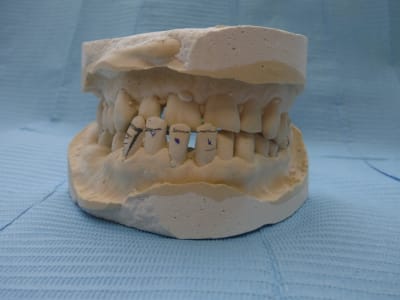

sans commentaire.

Ah si! 64 ans... et 41, 31 HS...

Lui 59 ans, 41 HS, c'est la semaine!!! les photos ne sont pas tops :-(